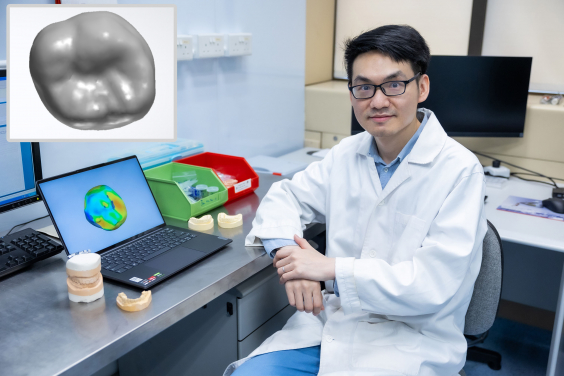

Project co-investigator Dr Hao Ding and the design of a personalised tooth crown using generative AI.

The researchers developed a generative AI algorithm that uses a true three-dimensional (3D) deep learning approach, producing personalised dental crowns with high accuracy that mimic the morphology and match the materials required for the biomechanics of natural teeth. Biomechanical finite element analysis revealed that by using lithium silicate, the AI-designed crown can come very close to achieving the expected lifespan of natural teeth. In contrast, the two existing methods of designing dental crowns result in crowns that are either too large or too thin, and fall short of matching the same lifespan as natural teeth.

The results have been published in leading academic journal Dental Materials in an article titled ‘Morphology and mechanical performance of dental crown designed by 3D-DCGAN’.

“We used a 3D-DCGAN (3D-Deep Convolutional Generative Adversarial Network) approach to ‘teach’ the AI algorithm ‘good’ designs by feeding the algorithm with over 600 cases of natural and healthy dentition. The algorithm improves the quality of the design through internal competition between a generator and a discriminator,” said Dr Hao Ding, a co-investigator on the project.

The 3D-DCGAN AI-designed crowns were compared with natural teeth and with two other conventional CAD methods of crown design methods. The results revealed that the generative AI-designed crowns had the lowest 3D discrepancy, closest cusp angle (morphological feature), and similar occlusal contacts (functional feature) as compared to natural teeth.